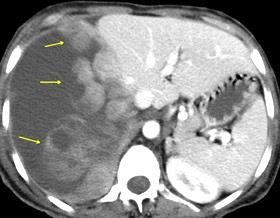

Densidad similar al músculo con estriaciones internas de grasa

Hallazgo incidental . Región infraescapular 2% de TC del tórax. Bilateral 60%.

Burt AM et al. Imaging review of lipomatous musculoskeletal lesions. SICOT J2017/ Murphey MD et al. From the archives of the AFIP: benign musculoskeletal lipomatous lesions. Radiographics. 2004